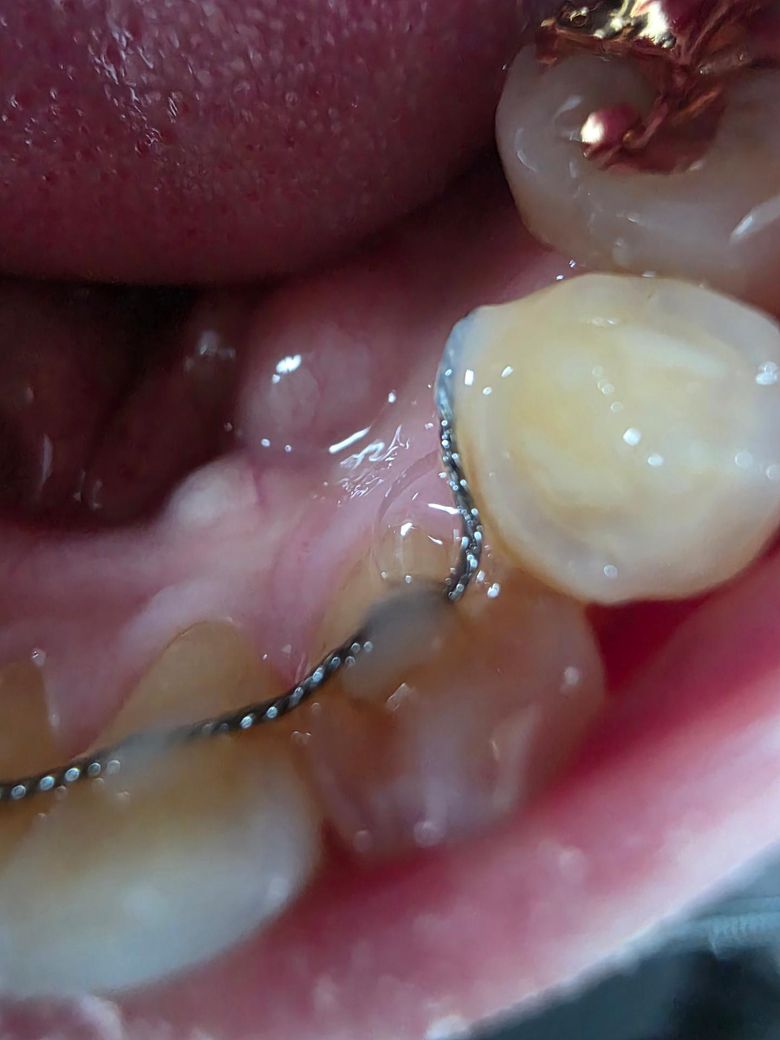

하악 와이어 왼쪽 끝 레진이 탈락해서 동네 치과의원도 아니고 병원에서 재부착하였습니다. 재부착하고 나서부터 치아뿌리에 가해지는 힘이 느껴지는데 이경우 치아가 틀어질 가능성이 있나요? 양쪽끝 와이어 재부착 시 잘못된 부착으로 인해 치아 파절 등 손상의 위험이 있는지 궁금합니다.

유지 철사가

상단 사진처럼 치아에서 떠있는 상태에서 고정이 되면 그럴 수 있구요

하단 사진처럼 최대한 치아에 붙은 상태로 고정이 되야합니다.

사진은 실제로 저희 환자분이 다른 치과에서 급하게 붙이시고 치아가 교정할때 처럼 느낌이 난다 하셔서 제거를 해보니 아니나다를까 와이어가 팍 튀어나갔던 경우입니다 ㅎㅎ